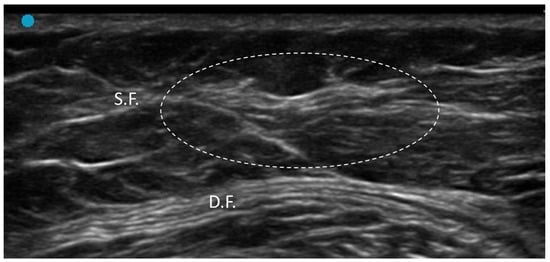

3.2.2. Densification

- Pirri, C.; Pirri, N.; Guidolin, D.; Macchi, V.; Porzionato, A.; De Caro, R.; Stecco, C. Ultrasound Imaging of Thoracolumbar Fascia Thickness: Chronic Non-Specific Lower Back Pain versus Healthy Subjects; A Sign of a “Frozen Back”? Diagnostics 2023, 13, 1436. [Google Scholar] [CrossRef] [PubMed] [PubMed Central]